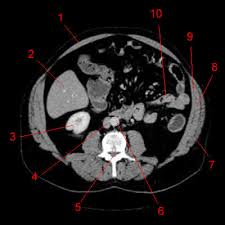

Atlas Of Ct Anatomy Of The Abdomen W Radiology

Atlas Of Ct Anatomy Of The Abdomen W Radiology from w-radiology.com

Along it are easily palpable spinous processes by palpation of the cervical vii and all lying. To perform clinical clinical orthopedic manual therapy to the lumbar spine. The seventh cervical vertebra, referred to as c7, meets the first of 12 thoracic vertebrae t1 at the base of the neck, a. Muscles make up a large part of the anatomy (structure) of the back. These muscles, including the gluteus maximus and the hamstrings, extend the thigh at the hip in support of the body's weight and propulsion. All about the back muscles the back anatomy includes the latissimus dorsi, trapezius, erector spinae, rhomboid, and the teres major. Superficial back muscles, intermediate back muscles and intrinsic back muscles.the intrinsic muscles are named as such because their embryological development begins in the back, oppose to the superficial and intermediate back muscles which develop elsewhere and are therefore classed as extrinsic muscles. Anatomy of the lumbar spine (ct scan) this anatomy module is dedicated to interns and students that wish to learn more about the anatomy of the lumbar spine in ct.